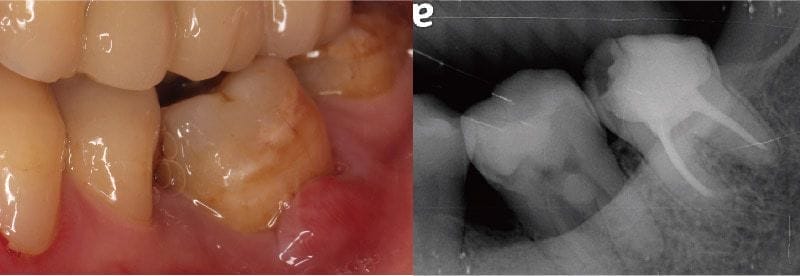

Mr.Lin最初因為左邊下面臼齒牙齦腫脹前來檢查,通常遇到這樣情況,確實很多人會懷疑自己是不是得了牙周病。經過X光片和牙神經活性檢查,我們發現該牙齒曾有大範圍填補,同時牙神經也無活性反應,其實這顆牙齒同時有牙髓和牙周的問題。

圖示:Mr.Lin左下臼齒牙齦近照與X光片,可看到大範圍填補痕跡和牙隨、牙周問題